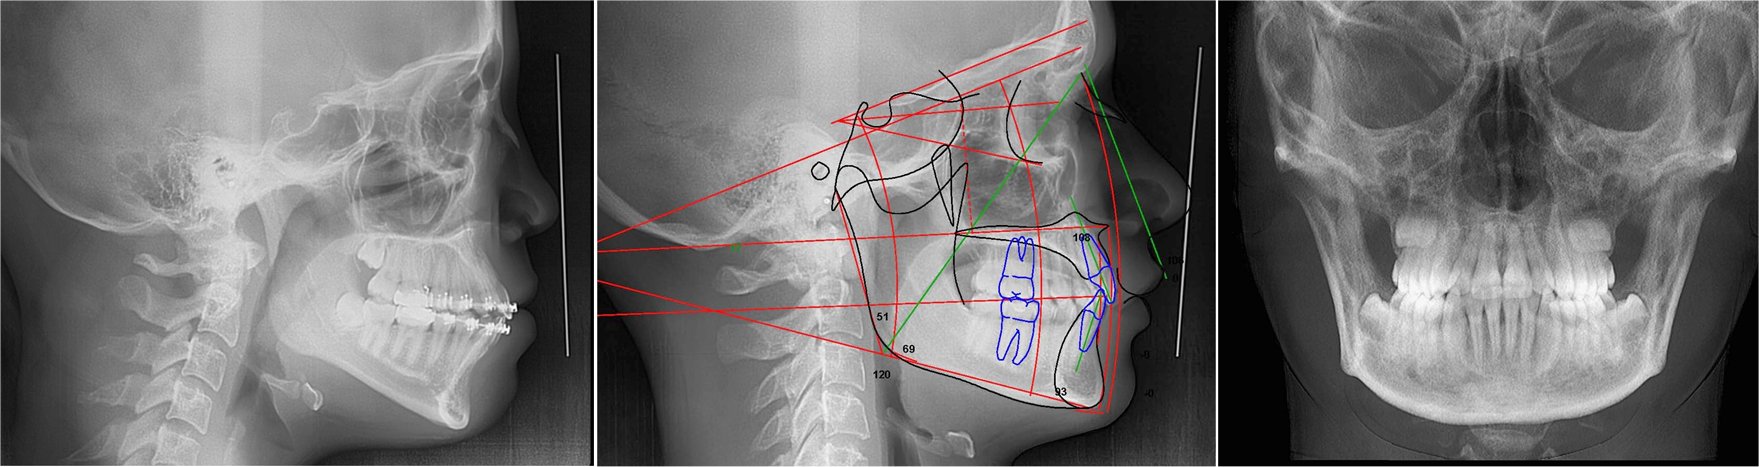

The Cephalometric 2D X-Ray Projection

These images are acquired in standardized lateral (side) and posteroanterior (front) projections. These views show the bone and soft tissues of the head, and are used to evaluate jaw growth and spatial relationships of the upper and lower jaws.

Show bone and soft tissues of the head from a side and front view. Measurements are taken from these images for dental, skeletal, and soft tissue analysis.